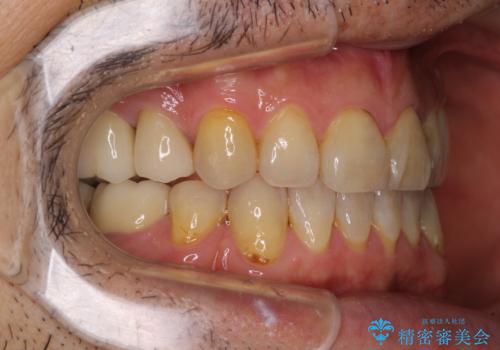

- むし歯による奥歯の痛みを気にして来院された患者様です。

神経にまでむし歯の及んでいる歯や、既に根管治療がされている歯に痛みがあったため、まずは根管治療を行うこととしました。

その後、以前行った抜歯矯正の後戻りをインビザライン・ライトにより改善し、むし歯や銀歯はオールセラミッククラウンにて補綴治療することとしました。

痛みは速やかに引き、銀歯や黒く変色したむし歯がセラミッククラウンで自然な色合いに仕上がり、患者様には大変満足していただきました。